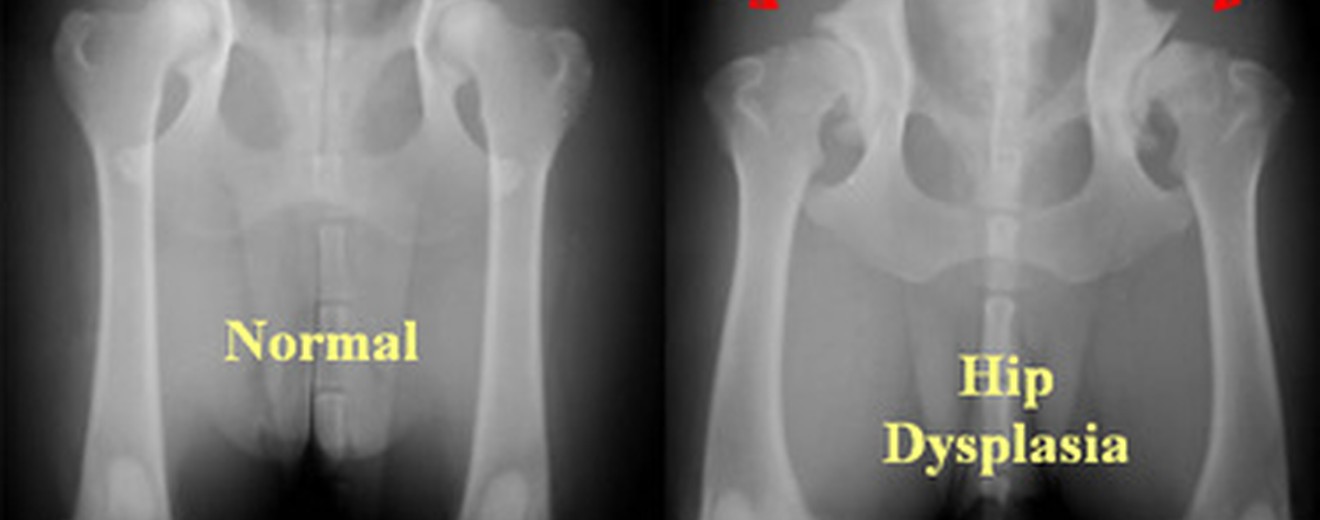

Kalça displazisi, büyük ırk köpeklerde yaygın kalıtsal bir eklem bozukluğudur. Kalça ekleği düzgün oluşmaz, gevşeklik ve kireçlenme (osteoartrit) gelişir. Bu rehberde, nedenleri, belirtileri ve tedavi seçeneklerini ele alacağız.

Belirtiler ve Teşhis

Veteriner hekim, fizik muayene ve röntgen ile teşhis eder. Erken evrelerde hafif belirtiler olabilir; ilerledikçe şiddet artar.